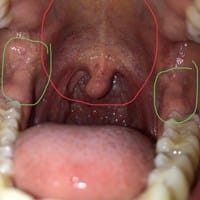

Hace 1 semana, tengo puntos rojos en el paladar, ¿Se debe a algo malo en mi salud bucal?

Tengo 16 años, hace 1 semana, presenté estos granitos en el paladar que están señalados de rojo, se dispersan hasta la úvula, no presento fiebre, mis amigadas no están inflamadas, ganglios linfáticos normales, pero se presencia punzada en la...